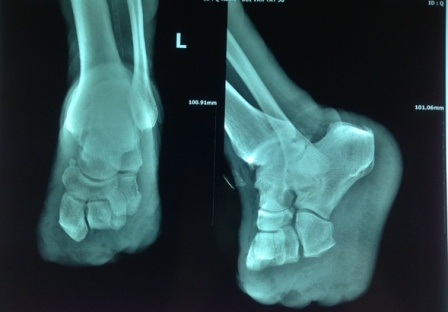

Đến khi vết thương bị bầm tím, chảy mủ, thân nhiệt tăng cao, gia đình mới vội vàng đưa đến bệnh viện địa phương kiểm tra rồi tiếp tục chuyển đến bệnh viện Chấn thương Chỉnh hình Sài Gòn - ITO ngày 5/3. Tại đây, qua các kết quả xét nghiệm, bác sĩ xác định bệnh nhân mắc bệnh tiểu đường tuýp 2. Đây là nguyên nhân khiến vết thương tưởng chừng vô hại song đã khiến ông T. bị nhiễm trùng, hoại tử bàn chân trái.

Bệnh nhân được điều trị tích cực bệnh lý tiểu đường và chăm sóc vết thương. Song trước tình trạng hoại tử diễn tiến ngày càng nặng không thể phục hồi. Các bác sĩ đã buộc phải thực hiện cuộc phẫu thuật tháo khớp đến nửa bàn chân trái để tránh nguy cơ nhiễm trùng hoại tử lan rộng có thể đe dọa tính mạng người bệnh. Hơn 1 tuần sau ca mổ, ngày 20/3 tình trạng sức khỏe bệnh nhân ổn định nên đã được bác sĩ cho xuất viện.